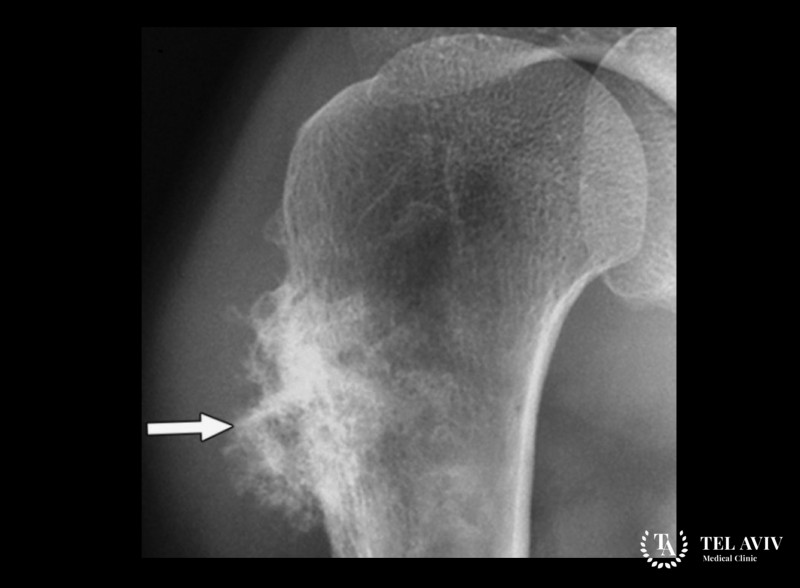

При подозрении на раковое заболевание костей необходимо проведение комплексного обследования, чтобы не только обнаружить злокачественную опухоль, но и оценить степень поражения тканей, стадию роста, возможные осложнения. Для этого в клинике Tel Aviv Medical Clinic используется высокоточное передовое оборудование, позволяющее получить максимум информации для последующего определения лечебных мероприятий.

- Рентген.